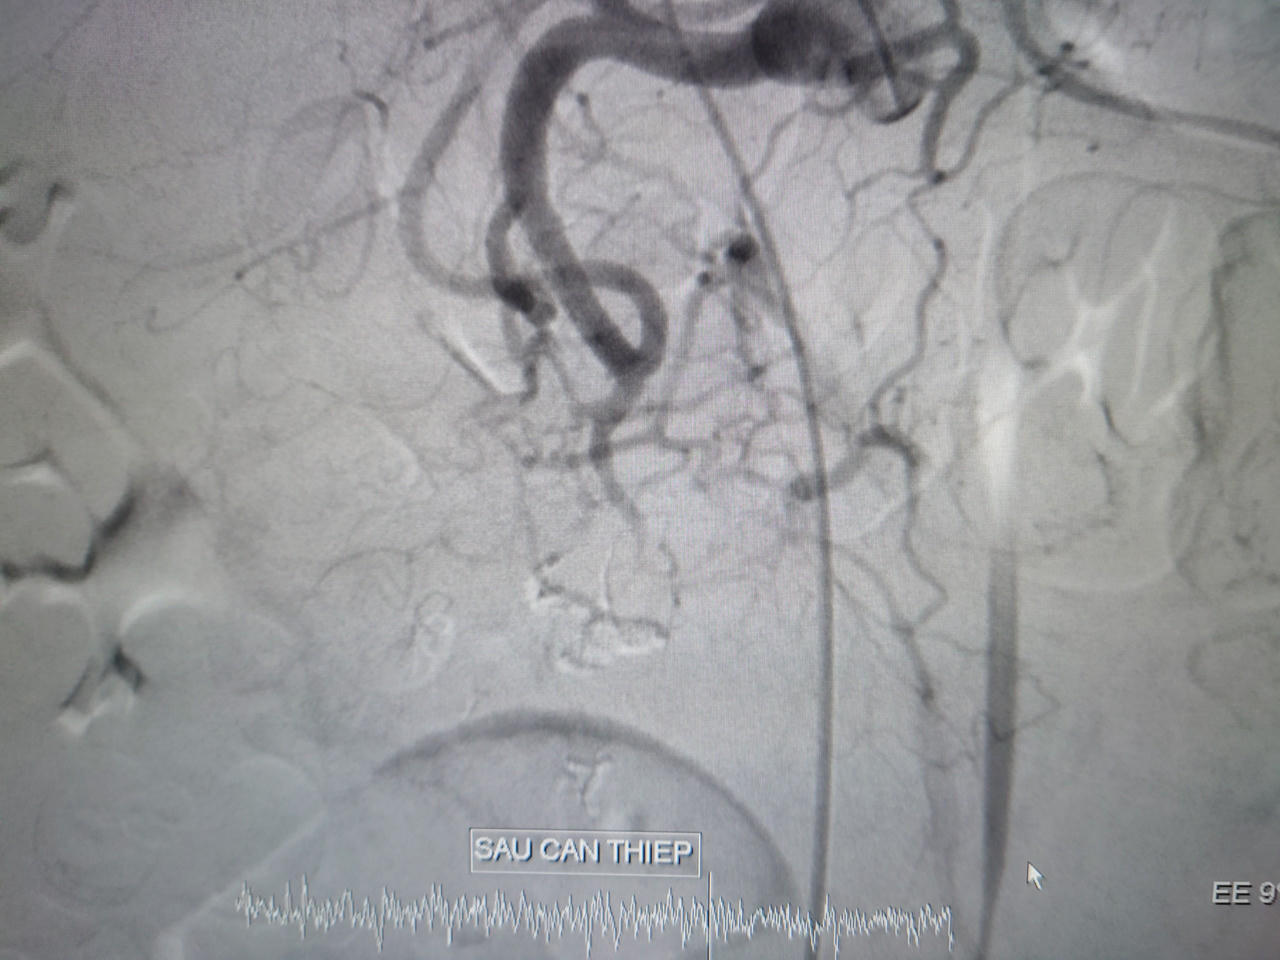

![]() |

Hình ảnh sau can thiệp |